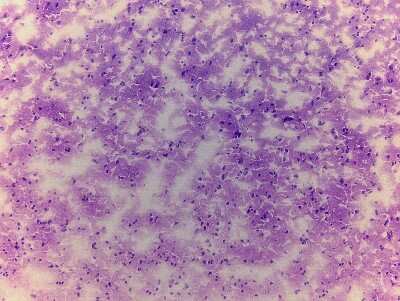

8 results for "Brain Postcentral Gyrus Slides and MicroArrays" in Products

Brain Postcentral Gyrus: Slides and MicroArrays